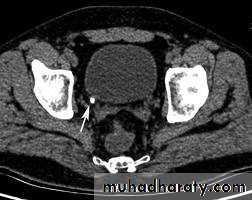

*Vesico ureteral junction stone on CT

*Phlebolith (arrow):-round lucent centre,,it represents calcified thrombus in pelvic vein.